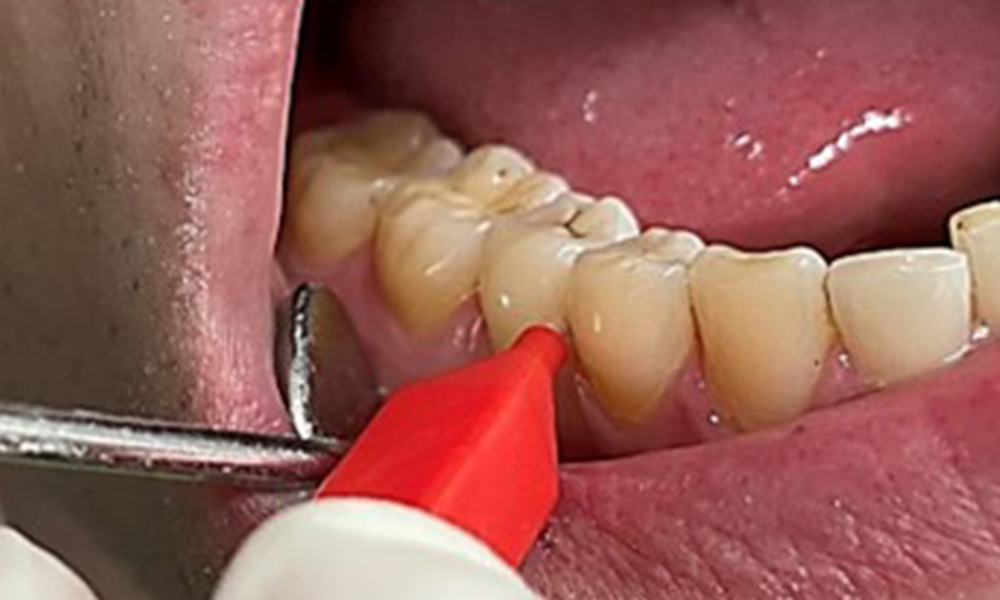

Il est également nécessaire de vérifier que les brosses interdentaires - utilisées quotidiennement par ce patient - sont de la bonne taille et encouragent une utilisation cohérente (Fig. 9). Une bonne hygiène intrabuccale minimise le risque de parodontite lié au tabagisme.